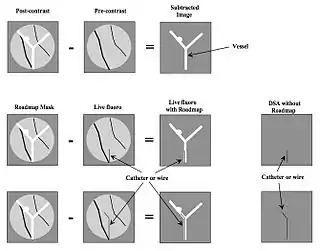

Digital Subtraction Angiography (DSA), as the name implies, involves an image subtraction technique - see Figure 7.1. As will be seen below, the technique involves more than simply applying a subtraction process in the digital image processor. In addition, it will be seen that the type of technology utilised, while based on the design of fluoroscopy systems, needs to incorporate a number of modifications unique to DSA. Before addressing the technology however, some basic physics needs to be introduced which will aid in putting the subsequent technology discussion into context.

- A second variation on the theme involves acquiring images of both the arterial and the venous vessels in the same region of the patient (e.g. the carotid arteries and jugular veins in the neck) so that when a mask image in the arterial phase is subtracted from a live image from the venous phase, a subtracted image showing both arterial and venous vessels can be generated. A third variation is referred to as Roadmapping - see Figure 7.7 - where an image at peak opacification is used as a mask and subsequent subtraction images, without injection of additional contrast medium, are used to guide advancement of a catheter or guide-wire.